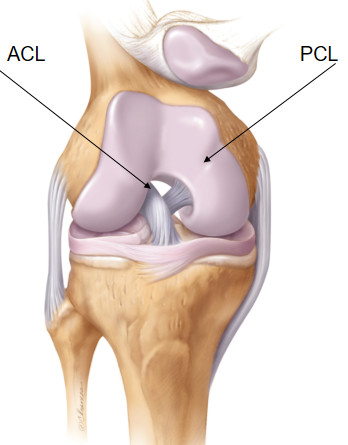

前交叉韧带的解剖

前交叉韧带(anterior cruciate ligament,ACL)起自于股骨外侧髁内侧面的半圆形凹陷处,然后经前内侧通过股骨髁间凹插入并附着于胫骨髁间隆起的前方,与外侧半月板的前中部相连;

股骨附着点位于股骨外髁的后内侧部,胫骨附着点位于胫骨髁间棘前侧与外侧半月板前角之间;

ACL走行比较陡直,倾斜角度至少应与Blumensaat线(股骨髁间窝皮质线,指股骨后侧面和ACL胫骨附着点之间的连线)相一致;

根据前交叉韧带胫骨附着点的位置将其分为前内侧束(anteromedial, AM)和后外侧束(posterolateral, PL)两部分。